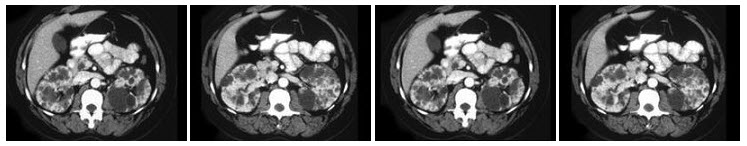

102、多项选择题

男,62岁,因排尿困难2年,加重伴二段排尿1月,CT扫描如图,下列说法正确的是()

A.膀胱后方可见多个囊性病灶

B.病灶壁薄,其囊内容物CT值与膀胱内尿液相同

C.增强后延迟扫描可见病灶内对比剂充盈,与膀胱之间可见一孔状通道

D.考虑为膀胱憩室

E.考虑为盆腔囊肿